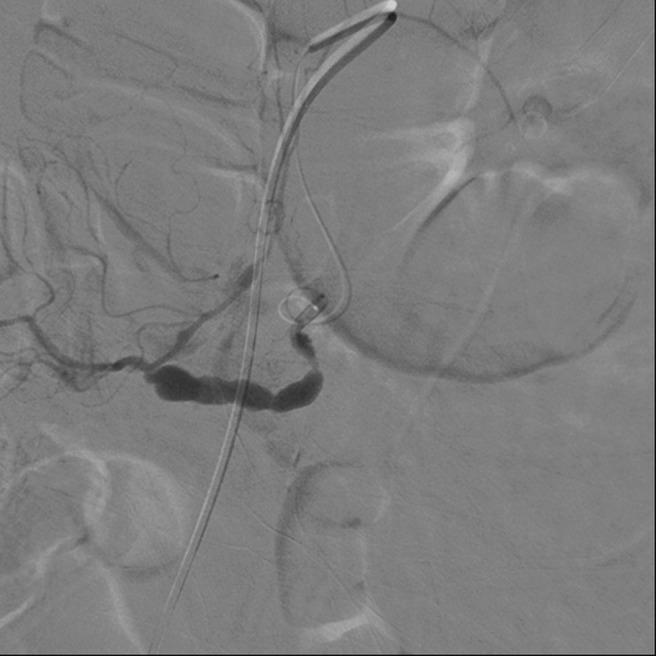

A 65-year-old male was brought to our hospital with right upper abdominal fullness sensation and recent body weight loss of about 3 kg. The patient had developed episodes of melena following progressive abdominal muscular guarding and drop of haemoglobin level to 6.3 g/dL. An abdominal computed tomography scan disclosed a ruptured hepatocellular cell carcinoma. A segmental arterial mediolysis was found on the superior mesenteric artery in the process of repairing the ruptured right hepatic artery with the assistance of angiography. Transarterial embolization was carried out and permanent haemostasis was achieved.